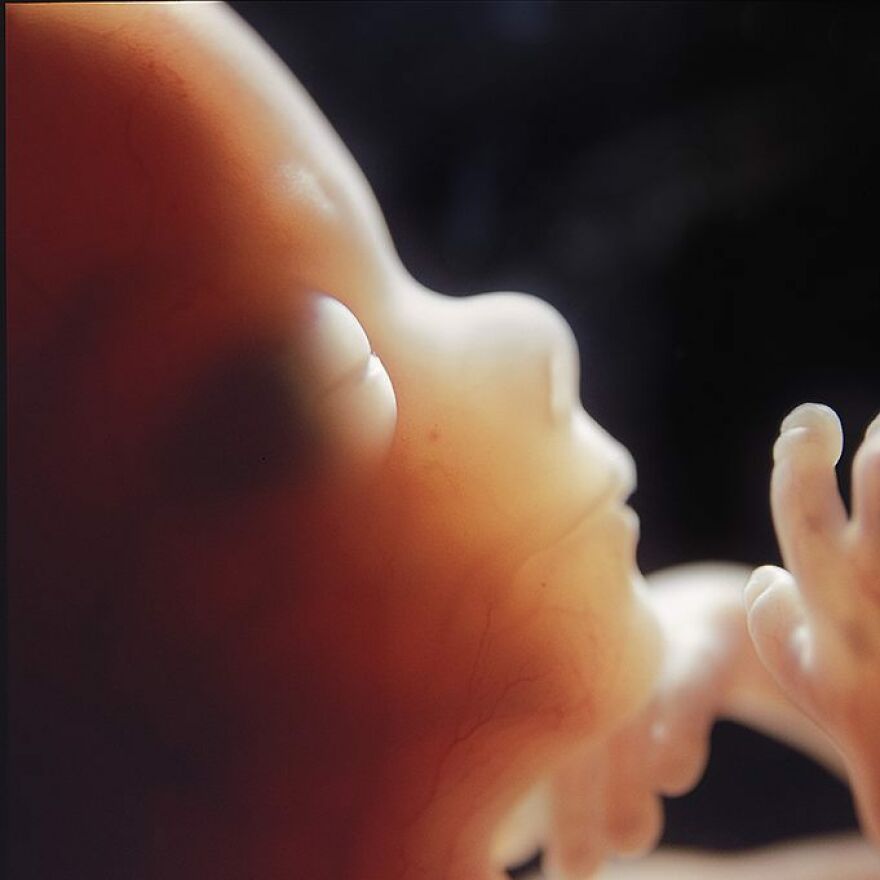

Fetus, 16 weeks, 1965

The network of blood vessels for the arm and hand is visible through the thin skin.